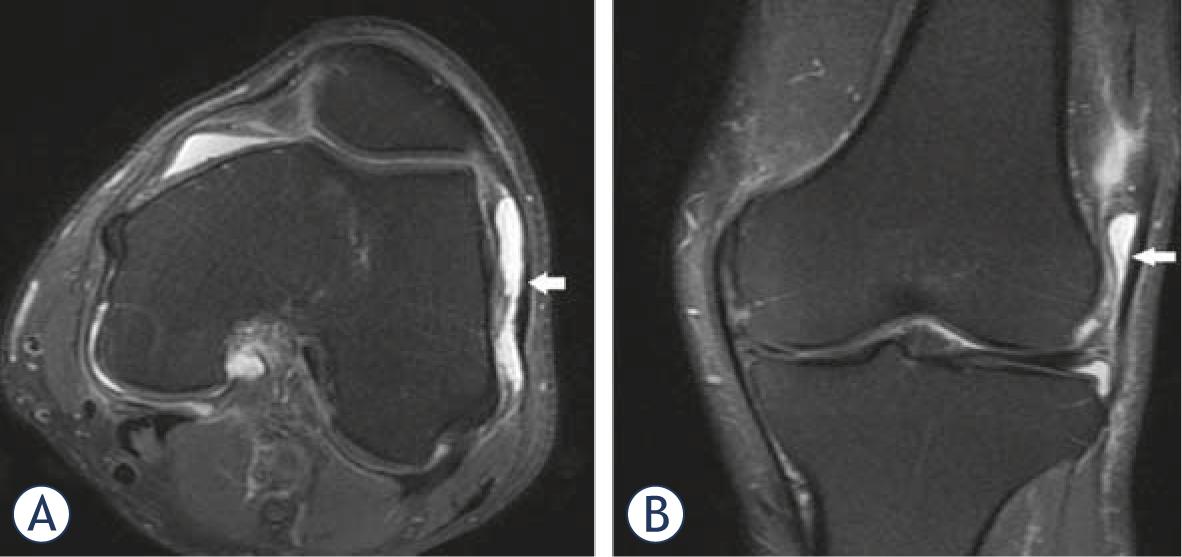

Positive correlation was present between severity of OA and CP (p = 0.03). Evaluation of lateral compartment bursae revealed lateral collateral bursitis in two patients and iliotibial bursitis in five (Figure 2 and 3). Prepatellar bursitis in the anterior compartment was determined in four patients, infrapatellar bursitis in four and suprapatellar bursitis in three. Additionally, synovial enchondromatosis was present in four patients, enchondroma in four and osteochondroma in one.

A 80 year-old patient presented with pain and tenderness in knee joint. Axial (A) and coronal (B) images demonstrate a fluid collection in the dilated iliotibial bursa.